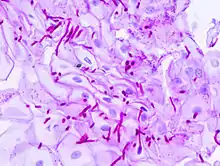

Candida Albicans Yeast forms (round-to-oval)

Candida Albicans Hyphal forms (filamentous projections called hyphaes emerging from round-to-oval forms)